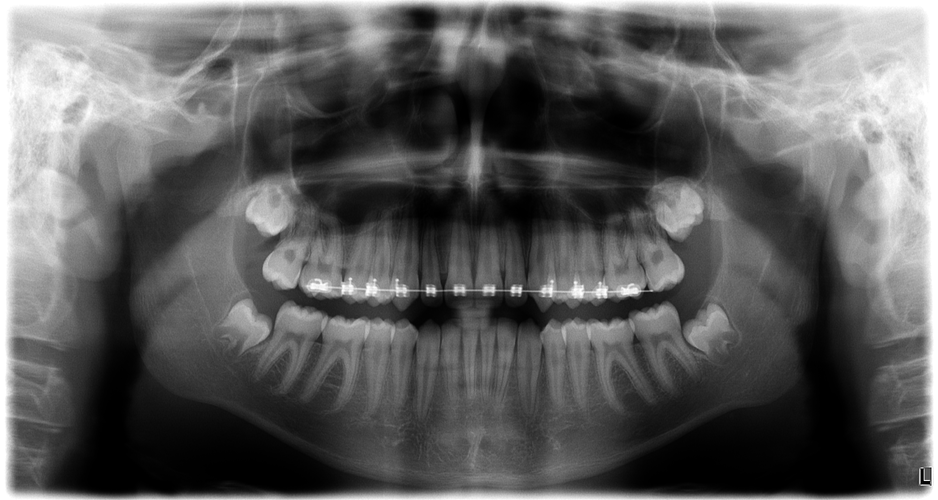

I'm thinking about getting my wisdom teeth removed, but I'm worried it might cause a recessed jaw or negatively affect my facial structure.Can wisdom teeth extraction cause jaw recession, or make the face look worse aesthetically?Also, if I don't remove them, they will ruin my teeth alignment.